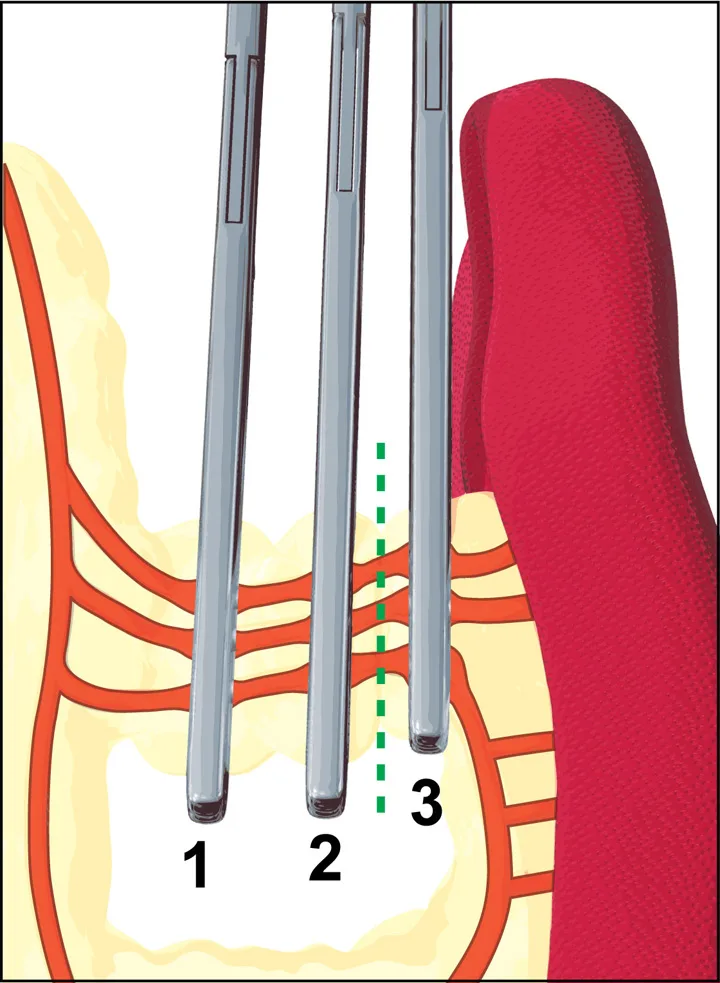

Three to 5 long, rather consistent primary blood vessel divisions of the splenic artery are the most important vascular structures to know before considering splenectomy (Figure 1). The most common textbook description for splenectomy includes individual ligation of short branches of the splenic artery and vein, preserving the left gastroepiploic artery and short gastric arteries, to maintain adequate gastric perfusion. In an experiment by Hosgood using healthy mixed-breed dogs, splenic and short gastric artery ligation during splenectomy did not compromise blood flow or the integrity of the stomach wall. Therefore, most surgeons are not concerned about ligation of these vessels, provided the stomach wall is not compromised. In conditions known to adversely affect gastric blood supply, such as acute gastric dilatation-volvulus, preservation of existing gastric perfusion during splenectomy is an important goal.

Diagram showing splenic arterial supply and 4 proposed ligation areas (blue lines).

The final 3 pedicles are isolated with the index finger, cross-clamped, and incised in the following order (refer to Figure 1): · Dorsal artery branch (Sometimes there are 2; be careful to preserve the left gastric epiploic artery located close to this branch.) · Main splenic artery terminating in the mid portion of the spleen · Caudal (omental) branch coursing along the tail of the spleen to the greater omentum.

Stack 3 crushing forceps (Carmalts) on the pedicle starting at the deepest aspect (during splenectomy the first clamp is closest to the stomach wall). The pedicle is severed between forceps #2 and 3 (dashed line).